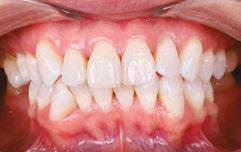

When the tongue rests in the palate, it impacts facial development especially for children who are still growing. An adult, for example, like our friend Stan, the progress made is gradual but more likely to last a lifetime. Generally, therapy starts out once a week for about 2-3 months. Then therapy progresses to every other week for 2-3 months, and then changes to once a month for about 5 months for the rest of the year. The exercises are done a minimum of 2 times everyday. These exercises are designed to strengthen and tone the orofacial muscles, building brand new neuromuscular function. When the muscles of the face are well developed, it may favorably impact appearance and the overall integrity of the facial structures. The muscles of the face also include the tongue, lips, cheeks and neck. Although the therapy program is typically only a year, Stan really liked how good he felt and decided to continue with some of the exercises to this day. From the photos you can see how much the program has impacted his health and well-being.

During his therapy, there was a discussion about the possible benefits he may receive from having his jaws expanded, making more room for his tongue, then to be followed by a tongue and buccal frenums release. His intermolar width is 34 mm, and his intercanine width is 25 mm. I feel any expansion has a potential benefit.

After completing his course of myofunctional therapy, he was able to open his jaws with full range of motion and achieve his goal of being able to enjoy some of his favorite foods again. He was most excited about being able to bite into a juicy cheeseburger.

Figure 4: 7 years later on April 10, 2024. Anterior open bite closed a bit